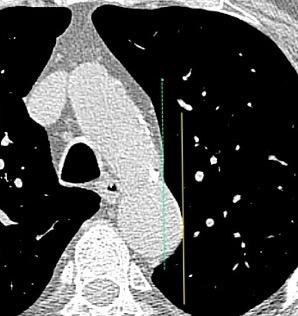

32 años .Preeclampsia a los 19. Hipertensión no controlada. Masa paravertebral sólida que se realza intensamente con afectación ósea.

Yue Y t al. Asymptomatic left posterior mediastinal functional Paraganglioma. A case report. Medicine . 2019